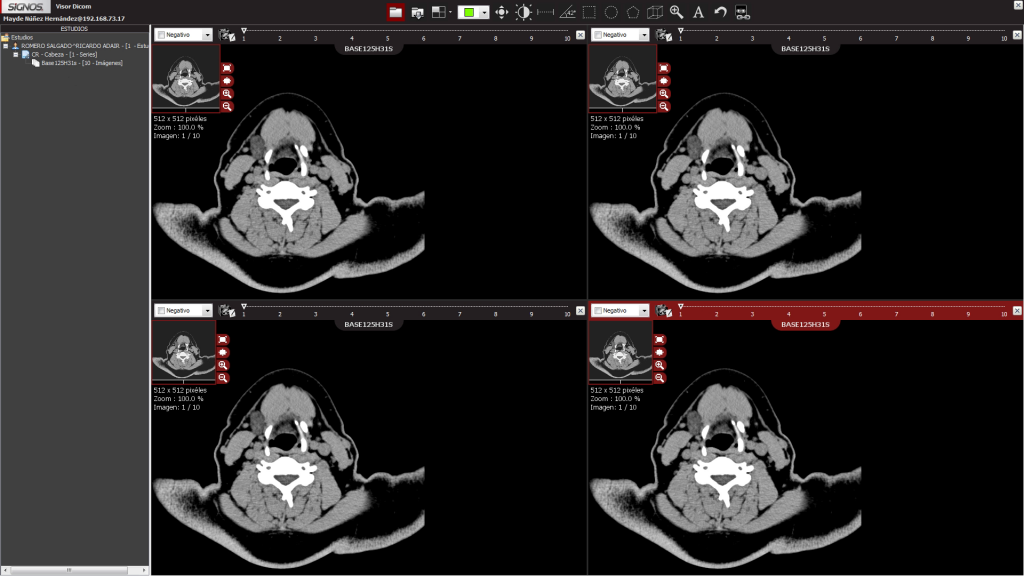

En la siguiente fase de trabajo, el grupo tuvo que atender una problemática identificada en las etapas anteriores; el reto estaba relacionado con la parte de imagenología porque el hospital contaba con varios aparatos de rayos X analógicos.

“Teníamos la necesidad de convertir la imagen analógica en una digital para integrarla a los expedientes, así que desarrollamos una interfaz para equipo comercial de digitalización y lo instalamos”.

Asimismo, los investigadores aprovecharon un vínculo entre el hospital de Lázaro Cárdenas y el Hospital Naval en Veracruz para desarrollar un sistema de diagnóstico a distancia para aquellos casos donde el hospital de Michoacán no contara con especialistas y pudiera ser apoyado por los doctores de Veracruz.

“En este punto era fundamental dar acceso al hospital de Veracruz a los expedientes clínicos de los pacientes en Lázaro Cárdenas para que se pudiera hacer el diagnóstico, así que se compartió el software desarrollado y se agregó el hospital de Veracruz a la red”.

Aun cuando ese proyecto se dio por concluido tras el periodo de evaluación, recientemente fue retomado por el doctor Altamirano Robles ante la oportunidad de implementar la misma red en una serie de nuevos hospitales en Puebla; no obstante, el trabajo no se limitará a la transferencia tecnológica, pues aprovechará para probar una serie de algoritmos desarrollados por diversos grupos de investigación del INAOE orientados al diagnóstico médico automatizado —con base en el análisis de imágenes.

Para concretar ese esfuerzo, se echará mano de proyectos que en el instituto se están trabajando desde hace varios años en torno al reconocimiento de imágenes, síntomas y características de enfermedades específicas.